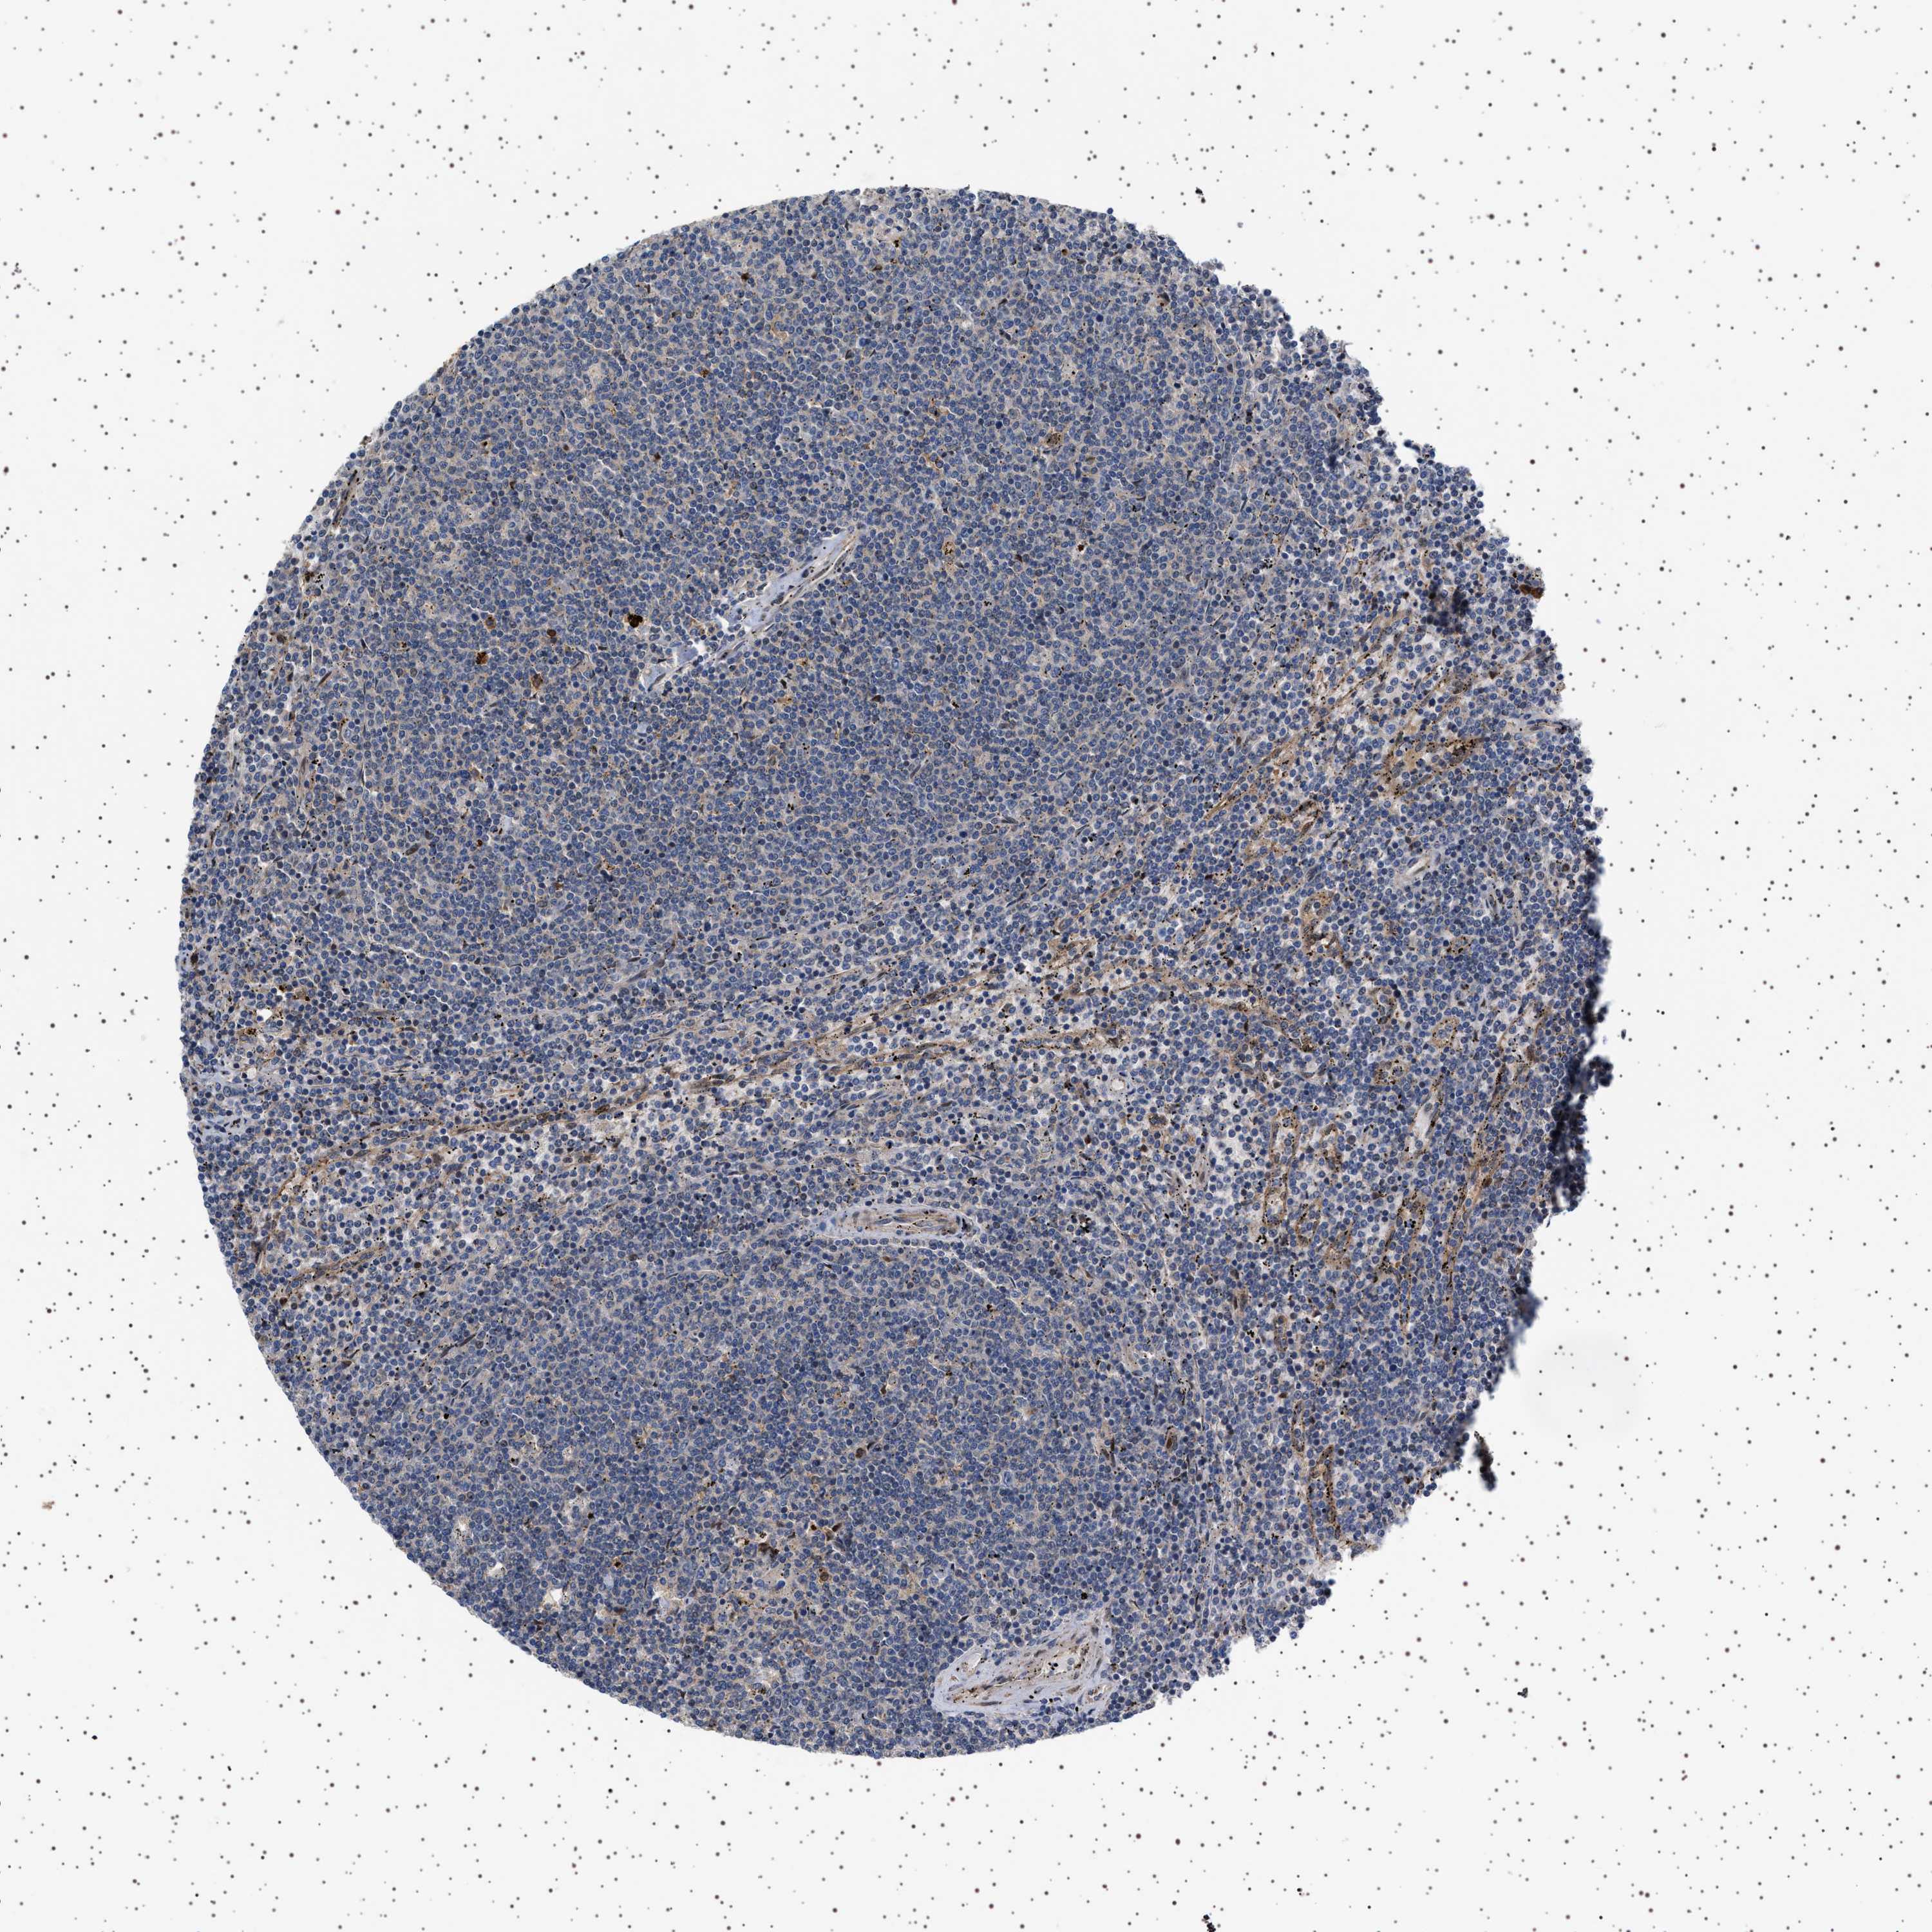

LYMPHOMA - Protein expressioni

A mouse-over function shows sample information and annotation data. Click on an image to view it in a full screen mode. Samples can be filtered based on level of antibody staining by selecting one or several of the following categories: high, medium, low and not detected. The assay and annotation is described here.

Each image is clickable and will lead to virtual microscopy that enables deeper exploration of all samples and also displays staining intensity scores, fraction scores and subcellular localization as well as patient and tissue information for each sample.

Antibody HPA018493

Hodgkin's disease, NOS

Malignant lymphoma, non-Hodgkin's type, High grade

Malignant lymphoma, non-Hodgkin's type, Low grade